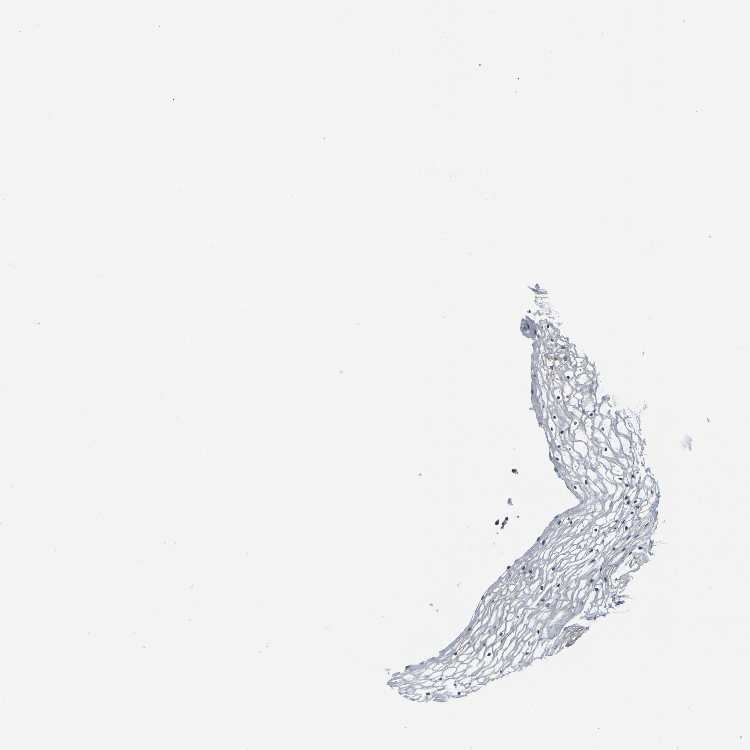

VAGINA - Antibody stainingi

Antibody staining in the annotated cell types in the current human tissue is reported as not detected, low, medium, or high, based on conventional immunohistochemistry profiling in selected tissues. This score is based on the combination of the staining intensity and fraction of stained cells.

Each image is clickable and will lead to virtual microscopy that enables deeper exploration of all samples and also displays staining intensity scores, fraction scores and subcellular localization as well as patient and tissue information for each sample.

Antibody HPA011088Antibody HPA012123Antibody CAB037128Antibody CAB037288

Squamous epithelial cells MediumMediumHighHigh